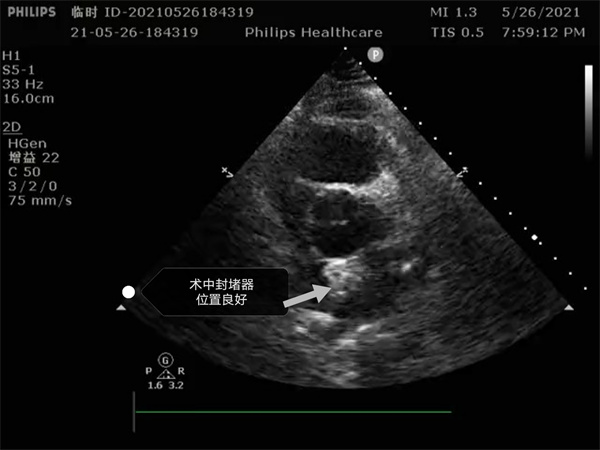

尤其是患者是个三房心,正常的人是有二个心房,这是一种少见的先天性心脏畸形, 如何在三房心把这个洞堵住,而且不影响心脏正常结构,是这个手术难点。沈主任组织全科进行术前讨论,5月26日下午5点开始手术,导丝如何在不规则的只有米粒大小的卵圆孔里通过,鞘管如何通过,如何进入卵圆孔连接的副房,避免封堵器夹住隔膜,这些难点在术中被沈主任团队一一化解,手术历时二小时,随着封堵器成功释放,导管室外响起来热烈的掌声。

就这样三房心合并卵圆孔未闭发生过三次脑梗的患者,在安康市中心医院心内科导管室成功进行了国内第二例介入封堵手术。